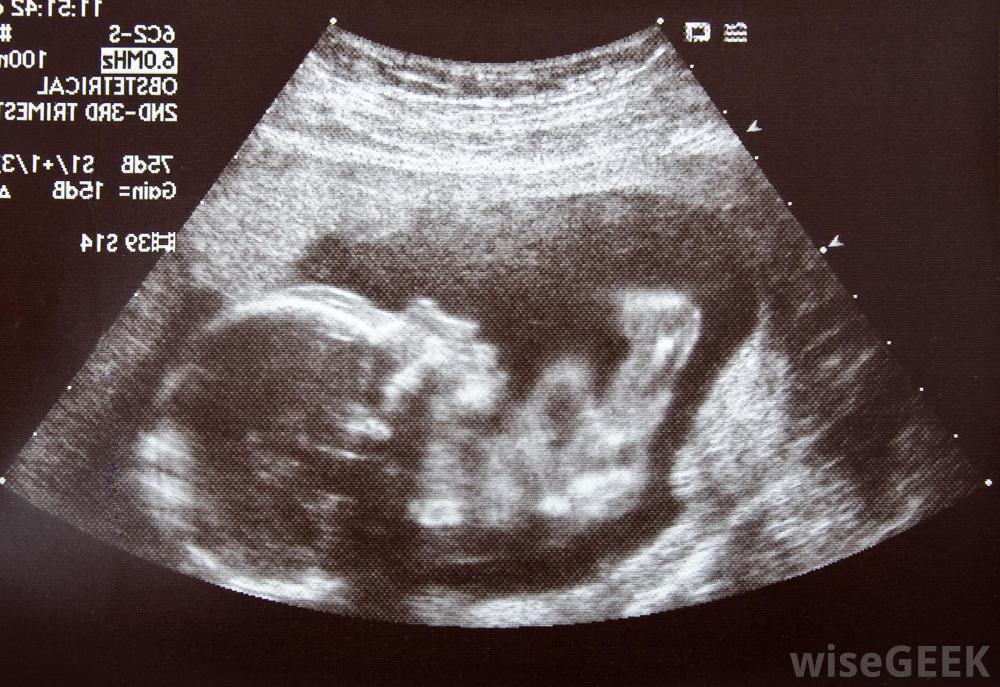

超声图像可以显示中期胎儿的生长特征怀孕的第四个月、第五个月和第六个月,孕中期通常标志着疲劳、恶心、晨吐和乳房压痛的消失。母亲会注意到身体的变化,包括皮肤变黑、乳房肿胀和宫缩乏力的表现,称为布拉克斯顿-希克斯宫缩。在怀孕的这个阶段,一些阴道分泌物是正常的。当身体调整以给生长中的胎儿腾出空间时,女性可能会感到臀部和骨盆疼痛和酸痛